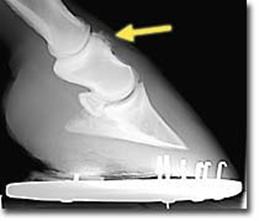

Kulno sąnario OCD (13 pav.) pasireiškia keliose skirtingose sąnario vietose: blauzdikaulio intermedialinėje keteroje, kulno distaliniame lateraliniame skridinyje, rečiau – blauzdikaulio plaktukėliuose ir kulno medialiniame skridinyje (Ross M.W., Dyson S.J., 2003, Bramlage L.R., 2006).

Diagnozuojant ligą, daromos 4 standartinės kulno sąnario rentgenogramos. Tai: dorsoplantarinė, lateromedialinė ir 2 įstrižos projekcijos. Iš jų dorsolateralinė ar dorsoplantarinė mediolateralinė įstrižos projekcijos suteikia daugiausiai informacijos (Ross M.W., Dyson S., 2003, Bramlage L.R., 2006).

13 pav. a) Medialinė įstriža kulnakaulio projekcija. b) Lateralinė kulnakaulio projekcija (cal.vet.upenn.edu ).